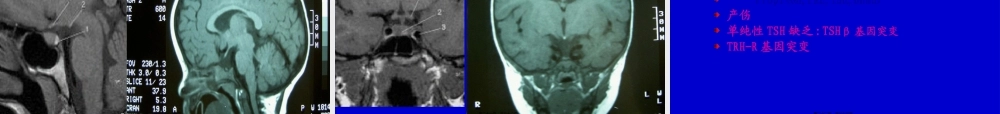

小儿甲状腺疾病重庆医科大学儿童医院内分泌科朱岷第一页,共七十六页。甲状腺功能低下症甲状腺功能亢进症甲状腺炎第二页,共七十六页。小儿甲状腺功能低下症第三页,共七十六页。小儿甲低分类先天性获得性散发性地区性暂时性永久性原发性→甲状腺继发性→垂体→下丘脑周围性→甲状腺素抵抗第四页,共七十六页。先天性甲状腺功能低下症(CH)最常见的小儿内分泌疾病之一:1/3500-4000最严重的后果→终生不可逆智力低下可预防性智力低下的最常见原因早期治疗可防止智力低下新生儿筛查使早期诊断治疗成为可能大多数为散发性,少数为家族遗传性,可为地方性(缺碘)最常见病因是甲状腺发育不良第五页,共七十六页。胎儿的甲状腺素分泌与生后变化甲状腺胚胎发育舌下的中央原基+两侧的第4咽囊移行致颈前(5-7周)甲状腺形成于12周,并开始摄碘甲状腺18-20周产生甲状腺素下丘脑-垂体-甲状腺轴建立并分泌TSH于18周第六页,共七十六页。胎儿的甲状腺素分泌与生后变化第七页,共七十六页。甲状腺激素与中枢神经系统发育胚胎早期致生后3-4岁是中枢神经系统发育关键期,甲状腺素作用相关基因起重要作用两个关键期孕后3月早期新生儿早期第八页,共七十六页。甲状腺激素与中枢神经系统发育胎儿期CNS发育相对独立于胎儿甲状腺,而与母体甲状腺功能密切相关无甲状腺胎儿出生时根本正常孕母甲低(严重缺碘,甲炎),胎儿CNS受损严重胎儿期CNS发育的保护机制母源性T4可通过胎盘胎脑富含二型脱碘酶,甲低时活性上调使T4→T3第九页,共七十六页。甲状腺激素与中枢神经系统发育生后及时替代治疗,可防止患儿的智力低下早期诊断治疗的重要性孕母甲状腺功能对胎儿脑发育的重要性对患甲状腺疾病孕母的甲状腺功能检查的重要性第十页,共七十六页。CH的病因甲状腺发育不全(原发性甲低)80%甲状腺素合成缺陷(原发性甲低)10%下丘脑-垂体性甲低(中枢性甲低)少见甲状腺素抵抗(周围性甲低),罕见暂时性甲低碘缺乏(地方性甲低)第十一页,共七十六页。CH的病因甲状腺发育不全(80%)T3↓T4↓TSH↑多为散发,其机制不明少为家族遗传:TTF1、TTF2、PAX8其中异位甲状腺60%(多为舌下),无甲状腺30-35%,正常位置发育不良甲状腺5-10%注意甲状舌骨囊肿中可有异位甲状腺第十二页,共七十六页。CH的病因甲状腺发育不全(原发性甲低)80%甲状腺素合成缺陷(原发性甲低)10%下丘脑-垂体性甲低(中枢性甲低)少见甲状腺素抵抗(周围性甲低),罕见暂时性甲低碘缺乏(地方性甲低)第十三页,共七十六页。甲状腺激素合成过程第十四页,共...